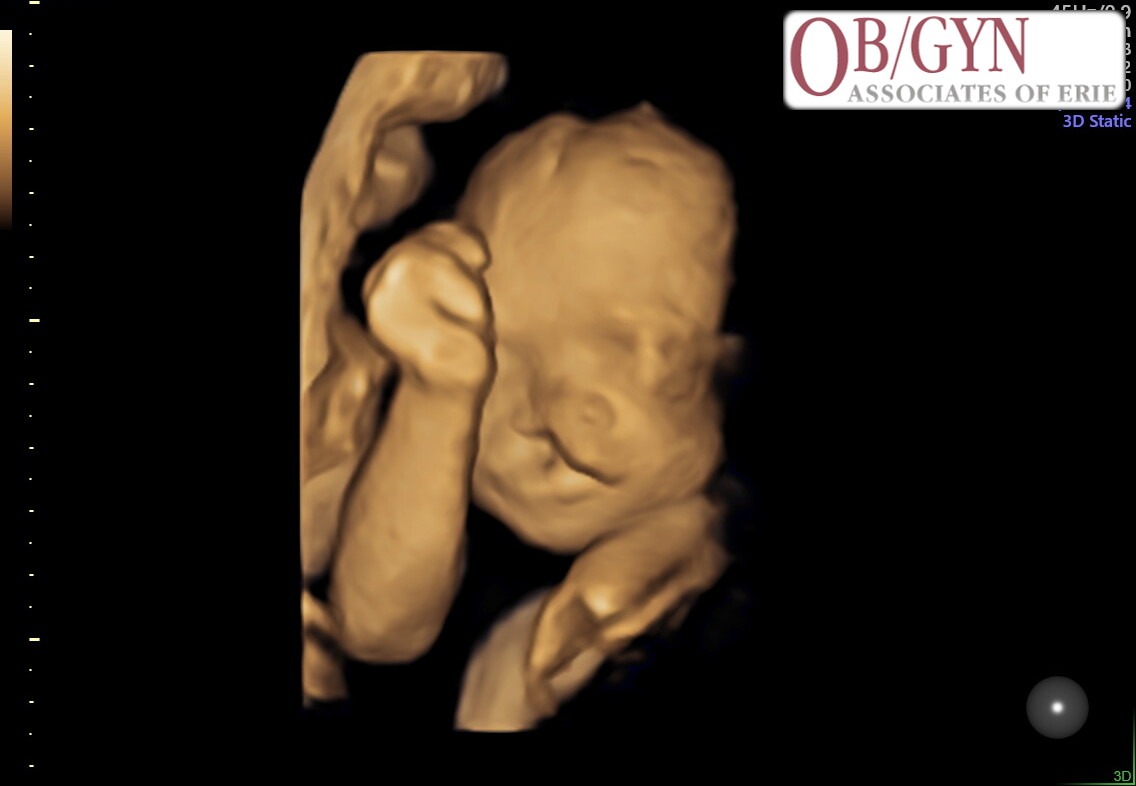

Recently, they received the news that sweet baby Dottie has been diagnosed with a cleft palate. While this condition is treatable, it will require multiple surgeries, specialized medical care, and ongoing follow-up appointments after she is born.